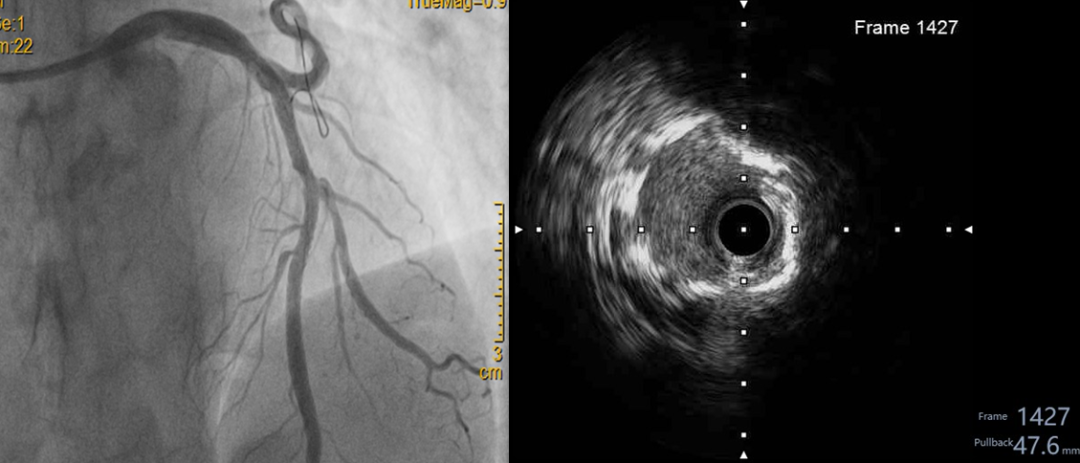

56 岁的白先生因反复胸痛在外院确诊为冠状动脉粥样硬化性心脏病,造影显示其前降支重度狭窄伴严重钙化。然而,传统球囊扩张技术因钙化斑块过于坚硬,手术被迫中止。转至我院后,心血管内科戴闽主任团队评估发现,若采用常规治疗,患者面临手术风险高、预后效果有限的双重困境。

经充分沟通,戴闽主任团队决定采用全球创新的震波球囊技术。该技术通过球囊内低频冲击波精准碎裂钙化斑块,如同"血管内的微地震",在不损伤血管壁的前提下软化"钙化坚冰",为后续治疗创造条件。医院紧急调配设备,确保手术顺利开展。术后造影显示血管狭窄显著改善,患者恢复良好。目前,白先生已顺利出院。

戴闽主任介绍,冠状动脉钙化病变是介入治疗的"顽固堡垒",易引发血管损伤等并发症。震波球囊技术的应用,使以往"无法介入"或"高风险"的病例获得微创治疗机会,为患者带来「心」希望。此次手术的成功开展,体现了我院在复杂冠心病微创治疗的技术积累与创新能力,未来将惠及更多钙化病变患者。」